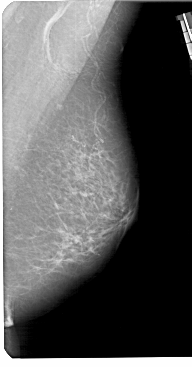

A_1306_1.LEFT_MLO

LEFT_MLO LINES 5491 PIXELS_PER_LINE 2626 BITS_PER_PIXEL 12 RESOLUTION 43.5 OVERLAY